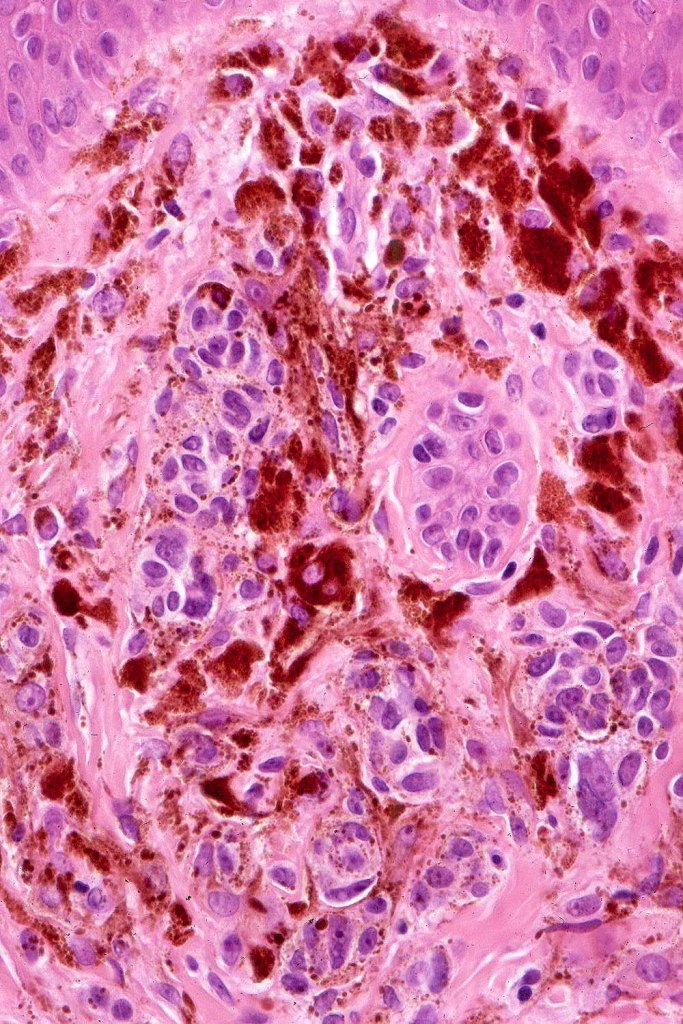

Combined Spitz & common blue nevus